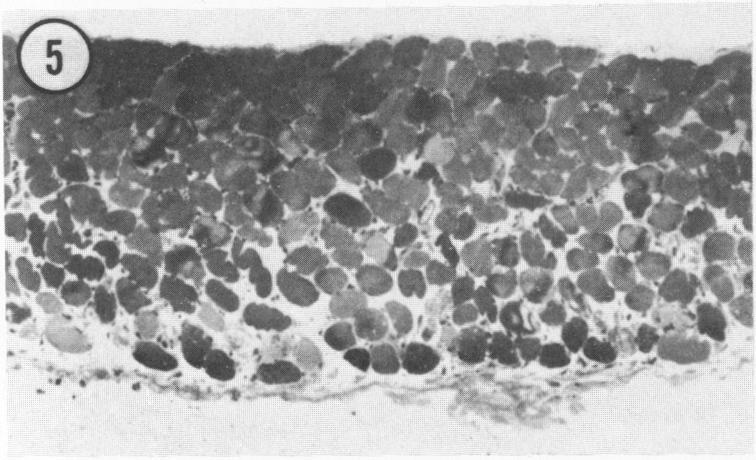

In this study, the authors examined the effect of the anti-tumor agent Adriamycin, a known cardiotoxin, on mouse heart, diaphragm, and gastrocnemius muscle. Using an established model of Adriamycin cardiac toxicity, they found that 4 days after the intraperitoneal injection of 20 mg/kg of Adriamycin, characteristic heart lesions, including vacuolation of the sarcoplasmic reticulum, interstitial edema, and mitochondrial degeneration, were demonstrated in all treated animals. Furthermore, similar, but much more severe, myocyte damage was demonstrated in the diaphragm; muscle toxicity followed a decreasing gradient of injury from the peritoneal to the thoracic surface of the tissue. On the other hand, treatment with Adriamycin resulted in an increase in the size and number of lipid droplets in the red fibers of the gastrocnemius muscle without any other ultrastructural evidence of drug-induced damage to myocytes. An examination of the pharmacokinetics and metabolism of Adriamycin after intraperitoneal treatment revealed that relative drug levels in muscle (diaphragm much greater than heart much greater than gastrocnemius) paralleled the degree of ultrastructural damage observed. This study indicates that treatment with Adriamycin can produce significant injury to non-cardiac muscle in a fashion that strongly resembles the characteristic pattern of Adriamycin-related damage to the heart, and that the degree of myocyte damage is apparently dependent upon the Adriamycin concentration in the tissue.

在本研究中,作者研究了抗肿瘤药物阿霉素(一种已知的心脏毒素)对小鼠心脏、膈肌和腓肠肌的影响。他们使用已建立的阿霉素心脏毒性模型,发现腹腔注射20mg/kg阿霉素4天后,所有接受治疗的动物均出现了特征性的心脏病变,包括肌浆网空泡化、间质水肿和线粒体变性。此外,在膈肌中也发现了类似但更为严重的心肌细胞损伤;肌肉毒性从组织的腹膜面向胸表面呈现递减的损伤梯度。另一方面,阿霉素治疗导致腓肠肌红色纤维中脂滴的大小和数量增加,而没有任何其他药物诱导的心肌细胞损伤的超微结构证据。对腹腔注射阿霉素后的药代动力学和代谢进行检查发现,肌肉中的相对药物水平(膈肌远高于心脏,心脏远高于腓肠肌)与观察到的超微结构损伤程度平行。这项研究表明,阿霉素治疗可对非心肌产生显著损伤,其方式与阿霉素相关的心脏损伤特征模式极为相似,并且心肌细胞损伤程度显然取决于组织中阿霉素的浓度。